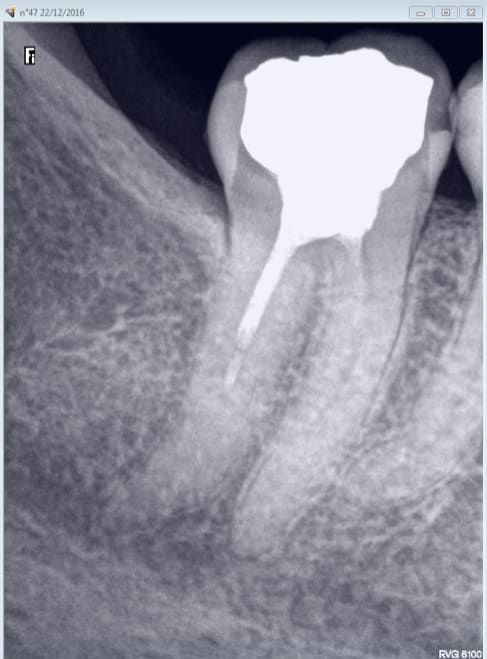

X ray 03 medium zvq18j - Eugenol